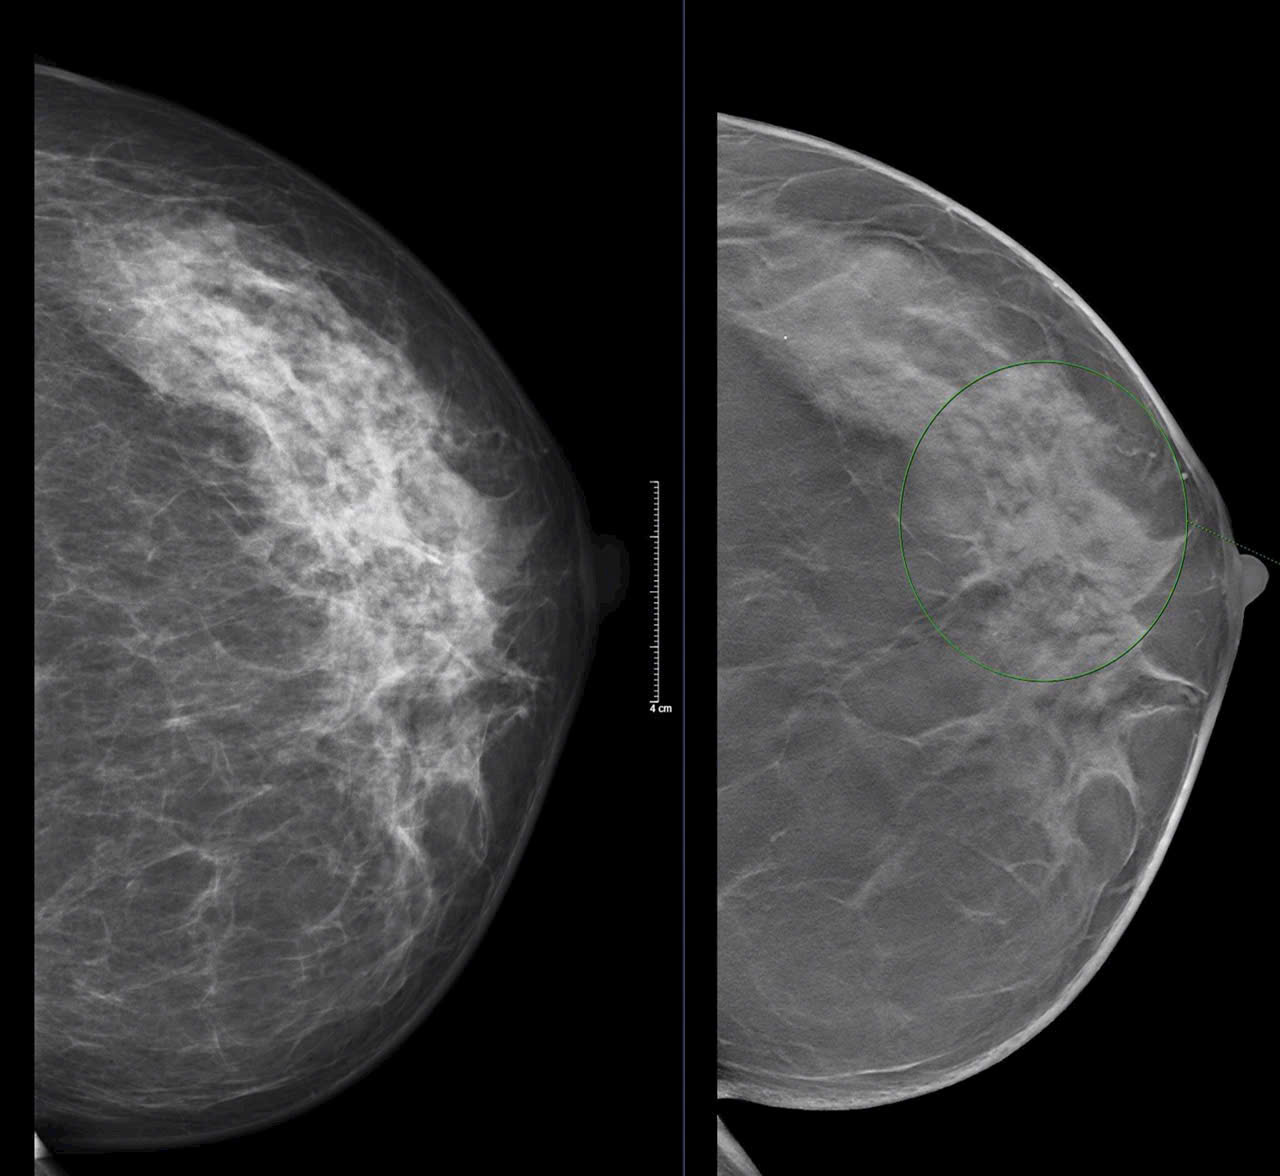

Mammocare – Sứ Mệnh Tiên Phong Trong Lĩnh Vực Tầm Soát Ung Thư Vú Tại Việt Nam

Mới đây, báo Sức khỏe & Đời sống đã có một bài viết giới thiệu về Mammocare, trung tâm tầm soát ung thư vú tiên phong tại Việt Nam, với sứ mệnh...